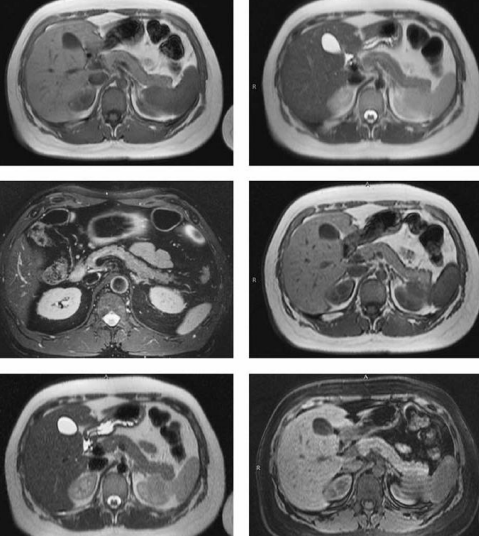

• Mejor método para vesícula, vías biliares y páncreas:

• ¿Cómo se ven los litos?

A

• COLANGIORM

• Hipointensos